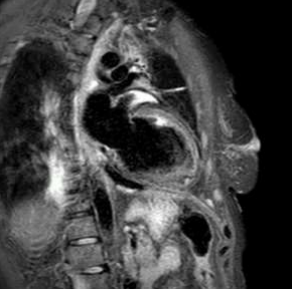

Cardiac magnetic resonance revealed left ventricle with characteristics of post-toxic cardiomyopathy and severely reduced global contractility with EF 34% (Image. 3- midmyocardial late gadolinium enhancement-LGE). Two chamber cine best visualized a cardiac mobile mass (11x7mm) attached to a small stalk to mid segment of the anterior wall of the left ventricle. The mass showed isointense signal on T1 (Image. 4), high intensity signal on T2 (Image. 5) and homogeneous late gadolinium enhancement (Image. 6). Characteristics were consistent with papillary fibroelastoma with differential diagnosis for myxoma or metastasis.

Image 5. CMR- high intensity signal on T2